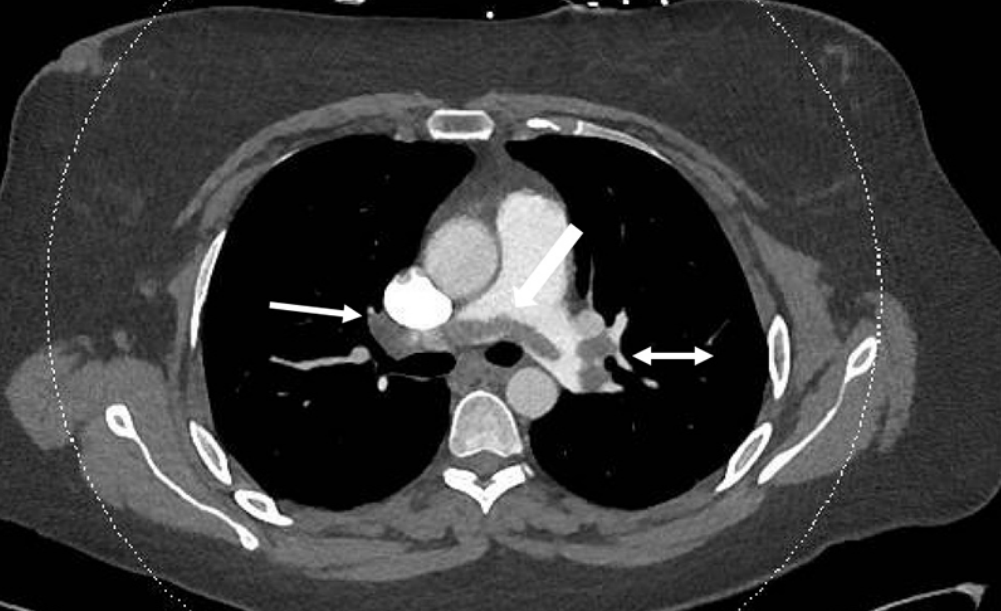

入院紧急行CT肺动脉造影(CTPA)显示骑跨型血栓延伸至双侧肺叶、肺段及亚段肺动脉分支,并伴有右心室劳损表现(图 1)。

图 1 CTPA示骑跨型血栓(粗箭头),延伸至双侧肺动脉分支。右肺动脉(单箭头)及左肺动脉(双箭头)血栓。